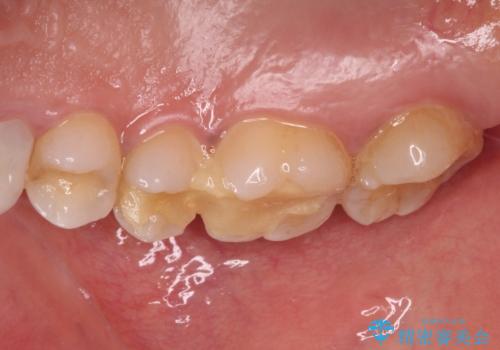

上顎臼歯は、おそらく銀歯を外して仮詰めされていたため、再度形を整え、セラミックインレーにて修復治療を行うこととしました。

奥歯は抜歯をせずに保存することができました。ただし、状態は決して良いとは言えないため、定期的に経過を見ていく必要があります。